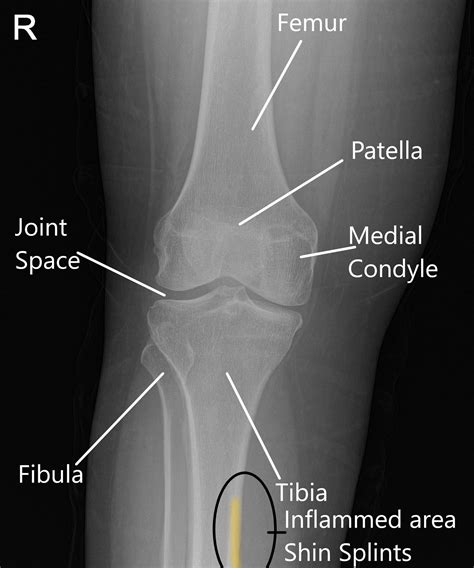

Shin Splints - Functional Physio SA